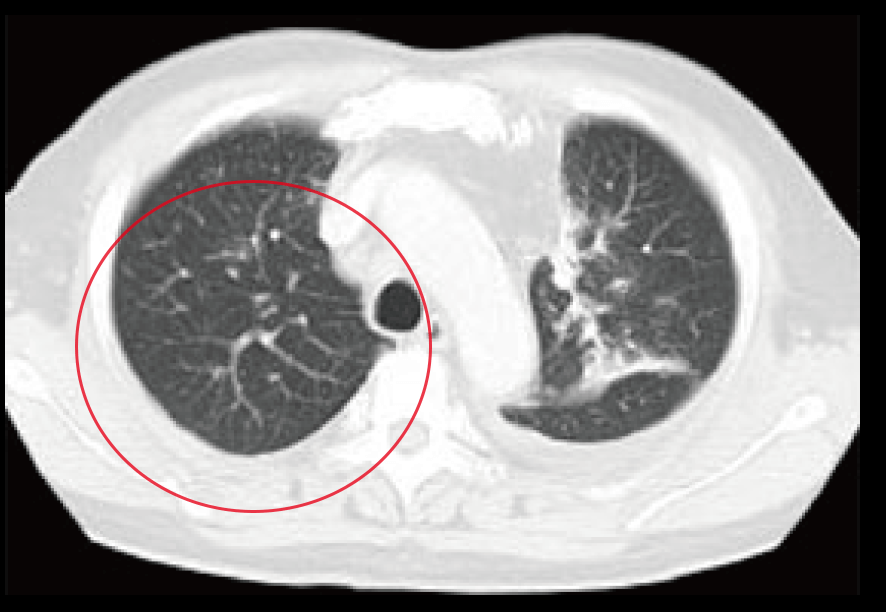

治療前CTでは右肺に大量貯留した胸水が認められる。

提示したCT画像はおよそ6カ月経過後の所見であり、貯留した大量の胸水はほぼ消滅。合わせて腫瘍マーカーもほぼ正常化したため、当外来での内服・点滴治療はいったん終了とした。 引き続き3カ月ごとの画像診断検査、6カ月ごとのリスクチェッカー検査(免疫採血)併用の必要性を指示した。